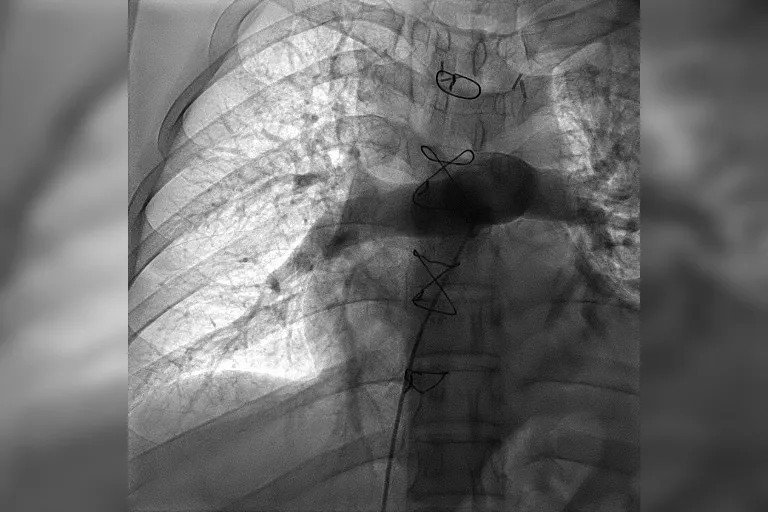

术前肺动脉造影术提示右肺动脉大面积血栓

时间就是生命。在我院快速急诊手术准备后,心内科副主任医师王承带着团队进入导管室。只见医生操作娴熟,选用新型取栓支架,灵活地经导管,一条一条地取出大量暗红色血栓。小章即刻感觉呼吸通畅,氧饱和度上升至95%以上。术后复查肺动脉造影术提示他的右肺动脉血栓影已完全消失,肺动脉血流通畅,各项血流动力学指标也明显改善。整台介入手术用时仅用30分钟,就立竿见影地让患者转危为安。

术后复查肺动脉造影术提示肺动脉血流通畅